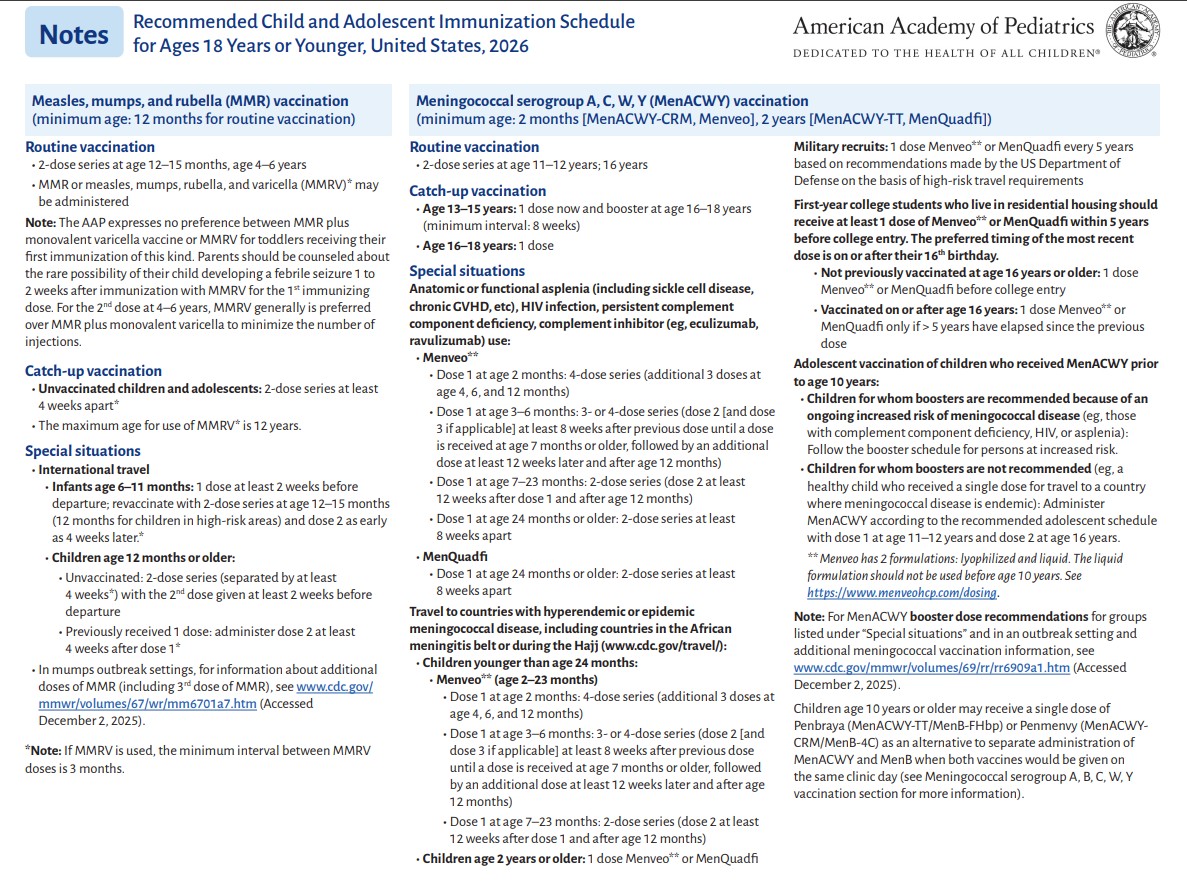

p 5

p 6

p 7

p 8